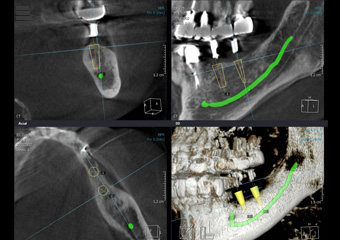

●歯ぐきに埋まっている親知らずをより安全に抜歯できる

●歯の根の形態や数などを立体的に捉え、根管治療に役立つ

●より精度の高いインプラント治療が可能

当院では、精密検査機器として「歯科専用のCT」を導入し、3次元撮影(水平・垂直・奥行)を行うことで、これまで十分に把握できなかった部分においても、より正確に診断できるようになりました。